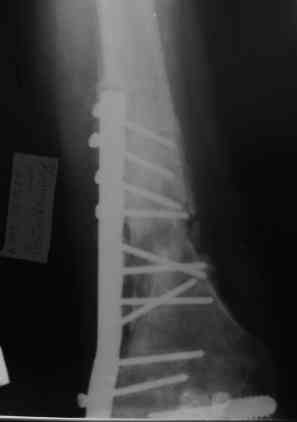

Не факт, что поможет. Вариант классический в стране ГА Илизарова - санация - удаление всего мертвого с резекцией и потерей длины - аппарат для сращения и восстановления длины в один или два этапа (судя по ситуации). Многократно опробован. Тем паче, что остеомиелит хоть и травматический (операционный), но не канальный-тотальный (от штифта), а достаточно локален (от пластины).

Штифт со спейсером предлагается не для санации тотального остеомиелита, а для создания депо антибиотика и уменьшения срока пребывания в аппарате Илизарова. А сам АВФ нужен по причине того, что изготовив спейсер на сплошном штифте, мы без ЭОПа вряд ли заблокируем дистальные винты, следовательно, не сможем избежать ротации на штифте по крайней мере два месяца.

Привет. Я имел в виду предложенную Вами программу лечения. Поражение кости остеомиелитическим процессом (судя по рентгенограммам) не канальное - когда спейсер можно поставить в канал после санации на какое-то время, а по всей окружности кости - когда придется делать спейсер в виде простой "болванки на арматуре). Вероятнее всего при хорошей санации получится дефект и укорочение. При втором этапе (как я понял, вы планируете БИОС) не факт, что восстановите длину и не "полыхнет" инфекция. Поэтому и предложена другая программа. Ваше право выбора - удачи на сложном пути избавления больного от ятрогенного о\миелита. Если проинформируете, что получилось, спасибо.